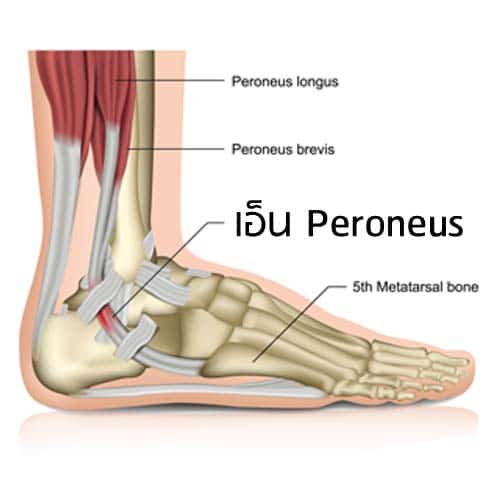

ปวดข้อเท้าเกิดได้จากหลายสาเหตุ ทั้งอุบัติเหตุ การใช้งานเยอะ และโรคข้ออักเสบ ชามใส่อาหารสัตว์ รูปกระดูก 2 ช่อง DBB342 – Cmpall.com

3 ระดับอาการข้อเท้าแพลง – Vejthani Hotpital รูปโครงกระดูกเวกเตอร์มือวาดตัวละคร PNG , โครงกระดูก, โครงกระดูกร่างกาย …

ข้อเท้าพลิกหรือแพลงเมื่อไหร่จะควรมาพบแพทย์ – คลินิกกระดูกและข้อ หมอวราห์ กระดูกสแคฟฟอยด์ ภาพประกอบ กราฟิกแบบเวกเตอร์ปลอดค่าลิขสิทธิ์ และคลิป …

เอ็นข้อเท้าอักเสบเกิดจากอะไร ? – คลินิกกระดูกและข้อ (หมอสุทธิ์) องค์ประกอบ Png เท้าเล็ก ๆ สีม่วงการ์ตูน ดาวน์โหลดรูปภาพ (รหัส …